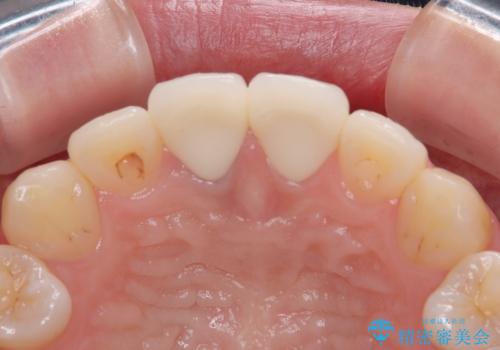

- 神経を取り除いた後に歯の色が変色して気になってきたとのことで来院された患者様です。

前歯は片側のみ神経を取り除かれていましたが、反対側もむし歯治療の詰め物が広範囲に及んでいたため、両方の歯をオールセラミッククラウンにて補綴治療を行うこととしました。

奥歯も著しく茶色に変色していたため、同様にオールセラミッククラウンにて補綴治療を行うこととしました。